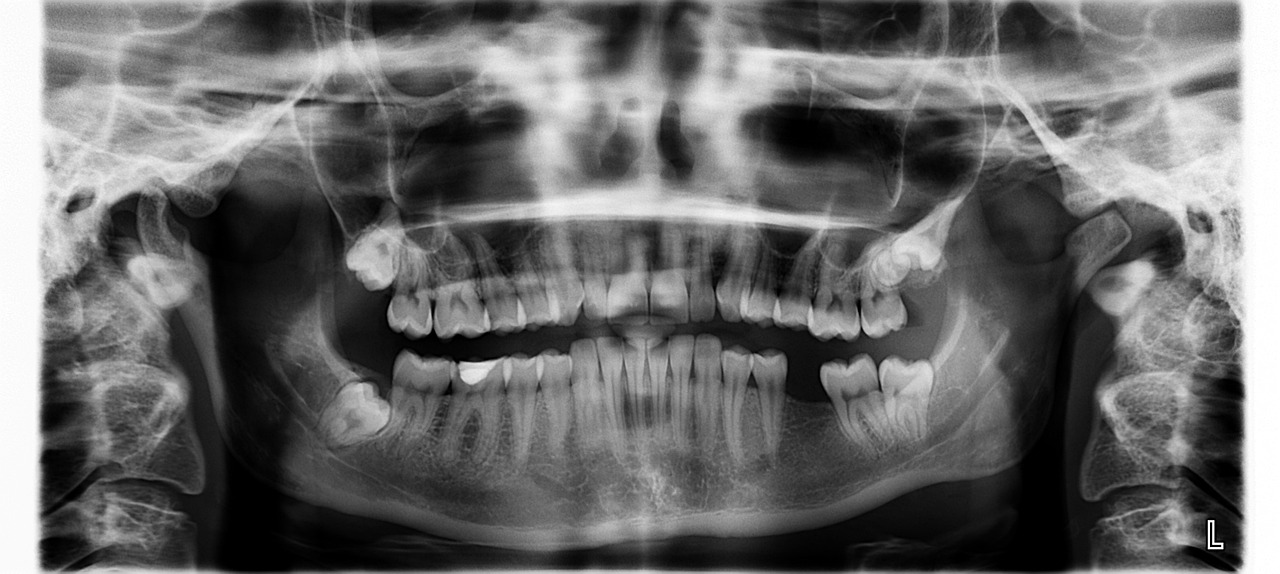

더불어, 사랑니가 주변 치아에 가하는 압력으로 인해 치열이 불균형해지고 통증을 동반하는 경우가 많습니다. 정기적인 치과 엑스레이 검사를 통해 사랑니의 성장 방향과 위치를 확인하며, 필요에 따라 조기에 발치를 권유받을 수 있습니다. 미루는 경우 감염 위험이 커지고, 인접 치아가 손상될 수 있으므로 적극적인 관리가 요구됩니다.